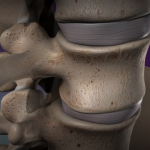

ALIF: Anterior Lumbar Interbody Fusion